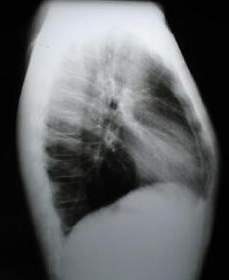

En la proyección lateral Izquierda (imagen de abajo a la derecha) se aprecia la protrusión esternal y en dirección anterior hasta la unión del tercio medio con el inferior, la retracción del xifoides, insinuando la estrechez de la base del tórax (Tórax en barril), el amplio diámetro anteroposterior del tórax se reduce en su extremo inferior.

Rx. Tórax Lateral Izquierda

La Rx lateral Izquierda del tórax muestra: la osteosintesis a nivel del 2 arco, la rectificación esternal, con la disminución del espacio retroesternal y el aumento del diámetro de la base del tórax en su extremo inferior.